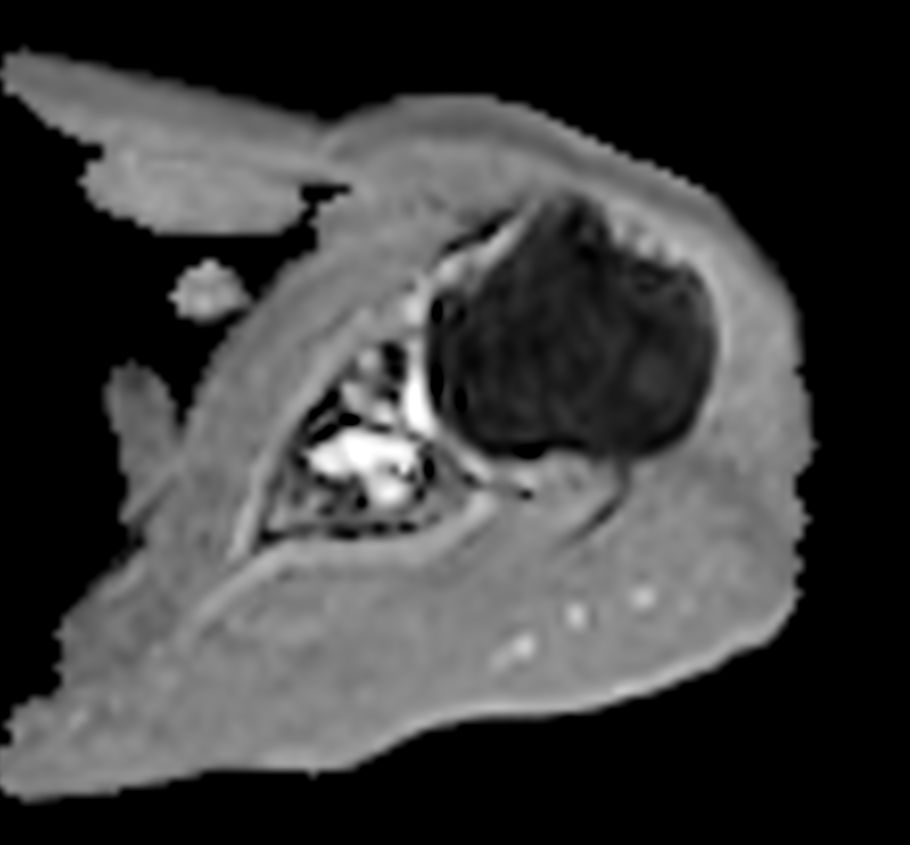

Patient with a shoulder tumor. Compressed SENSE acceleration is included to speed up sequences while maintaining equal image quality. mDIXON XD TSE in included (pre- and post-gadolinium injection) providing uniform, complete and consistent fat-free imaging. Besides the regular DWI EPI, a high resolution diffusion method is also included.

Axial PDw TSE

Axial T2w SPAIR

Axial T2w SPAIR - Compressed SENSE